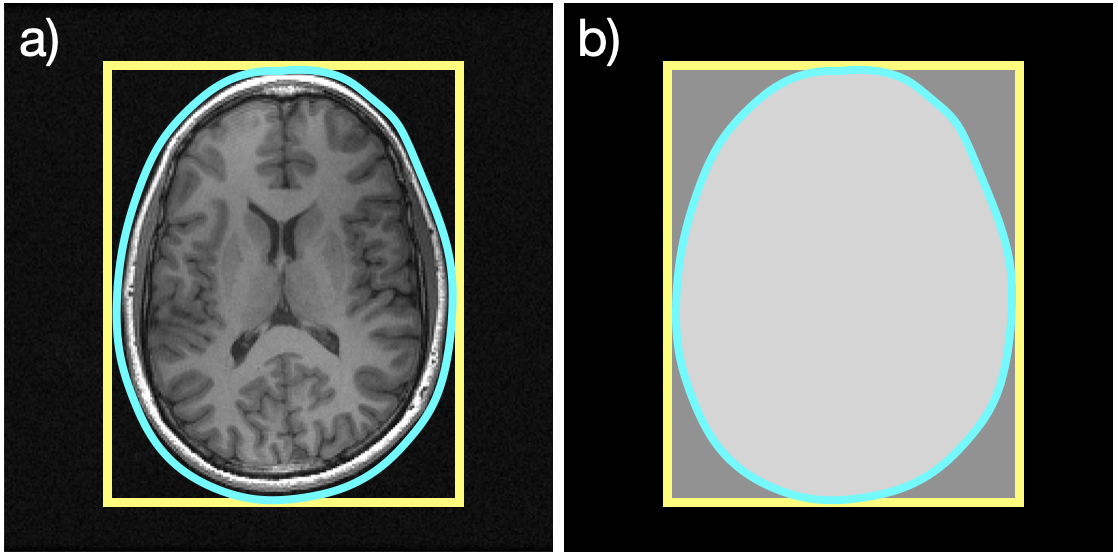

It is often the case, though, that the support of the object (i.e., the area where the object is present) to be imaged is significantly smaller than the FOV. Consider the axial slice of a brain shown in Fig. 1a; the yellow rectangle and cyan contour represent the boundaries of a rectangular and non-rectangular FOV, respectively. As shown in Fig. 1b, the area enclosed by the cyan contour is smaller than that of the yellow rectangle. It would seem, then, that fewer samples should be required for a high-quality image of the reduced FOV.

Figure 1: An axial slice of a brain: a) the yellow rectangle and the cyan contour represent a rectangular and non-rectangular FOV, respectively, and b) a depiction of the reduced area in the non-rectangular FOV.